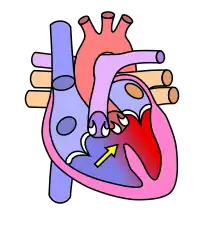

Shunt droit-gauche

Le sang non oxygéné passe dans le ventricule gauche, causant une cyanose[1]

Schéma sur les localisations des communications interventriculaires (légende) :

- CIV membraneuse et péri-membraneuse (1-2-3)

- CIV d'admission ou postérieure (4)

- CIV musculaire ou trabéculée (5-6)

- CIV sous-aortique (7)

- CIV infundibulaire (8).

Anecdote : les CIV « infundibulaires », c'est-à-dire siégeant sous les valves pulmonaires sont fréquentes en Asie alors qu'elles sont très rares en Europe où elles pourraient être un lointain souvenir des invasions barbares. Elles ne se ferment jamais spontanément.